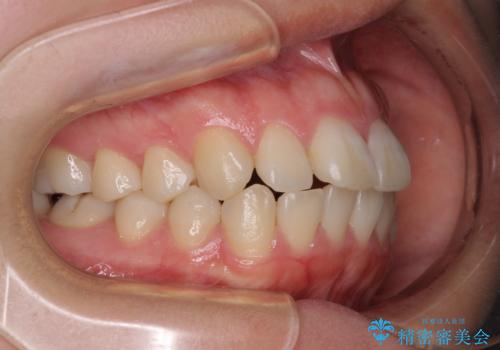

- 口元の突出感を気にして来院された患者様です。

口元を積極的に引っ込めるために、上下左右の第一小臼歯を4本抜歯することとし、ワイヤー装置による矯正治療を行うこととしました。

上下前歯がくちばしのように突出していましたが、抜歯矯正により口元が引っ込み、唇が閉じやすくなり、鼻の下の膨れた感じも解消されました。